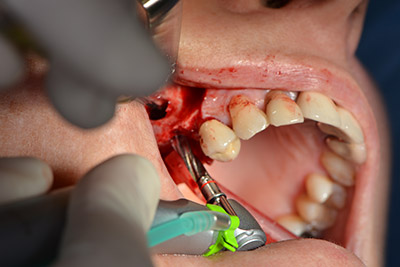

Surgical procedure for implantation

pilot drilling

Image 9: Overview and setting for pilot drilling.

The classic incision (crestal, buccal relief) and the preparation of the mucoperiosteal flap enabled a good overview.

Sky implants (bredent) were used this case. The surgical protocol of these, specify pilot drilling at about 1200 rpm (Fig. 9).

The following holes were drilled at a reduced speed of 300 rpm. The Implantmed demonstrated its true capability at this stage. The surgical protocol can be preset – the various positions can be selected simply by pressing the “P” position of the foot control (Fig. 10 to 11).